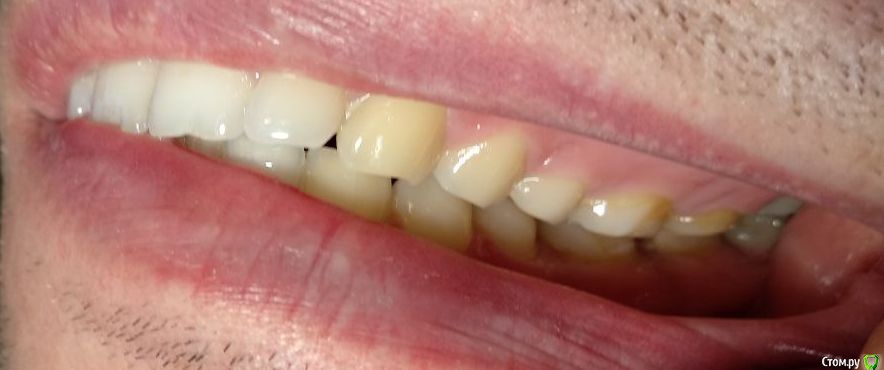

Здравствуйте! Откололся кусок зуба. 8 октября сделали КЛКТ (3Д снимок всех зубов). Вскрыли зуб, была проведена девитализация. Поставили диагноз: хронический фиброзный пульпит 37 зуба. 18 октября было проведено первичное лечение 3-х канального зуба эндомотором с использованием микроскопа и системы коффердам. Все каналы были запломбированы гуттаперчивыми штифтами на силлере методом латеральной конденсации Adseal, внутрь заложена ватка и поставлена временная пломба дентин-паста. 29 октября ортопед №1 посмотрел прицельный снимок (см. снимок зуба 2) и сам зуб, пломбу не снимал. Озвучил, что у меня низкая высота зуба, мне нужно установить культевую кобальт-хромовую вкладку и сверху покрыть металлокерамической коронкой зуб. Также сказал, что циркониевая вкладка мне не подходит из-за высоты. Однако, поскольку ортопед №1 уходил на обучение, мне было предложено обратиться в другую клинику к другому ортопеду. 1 ноября ортопед №2 посмотрев мой зуб без снимка заявил, что у меня сохранились три стенки у зуба и мне надо просто закрыть пломбой этой зуб. Поскольку ортопед №2 предложил диаметрально противоположное лечение зуба, то я решил обратиться в третью клинику. Ортопед №3 посмотрев снимок моего зуба, сам зуб, в том числе внутри (снял мою временную пломбу из дентина), заявил, что у меня низкая высота зуба и мне нельзя ставить культевую вкладку и коронку. И было предложено сделать вкладку из пресс керамики overlay. Также когда удалили временную пломбу у меня увидели кариес на этом зубе. В конце приема мне взамен снятой пломбы установили временную пломбу парасепт.

Сделал несколько фотографий, тк не совсем понял с какого ракурса делать фото с сомкнутыми зубами.